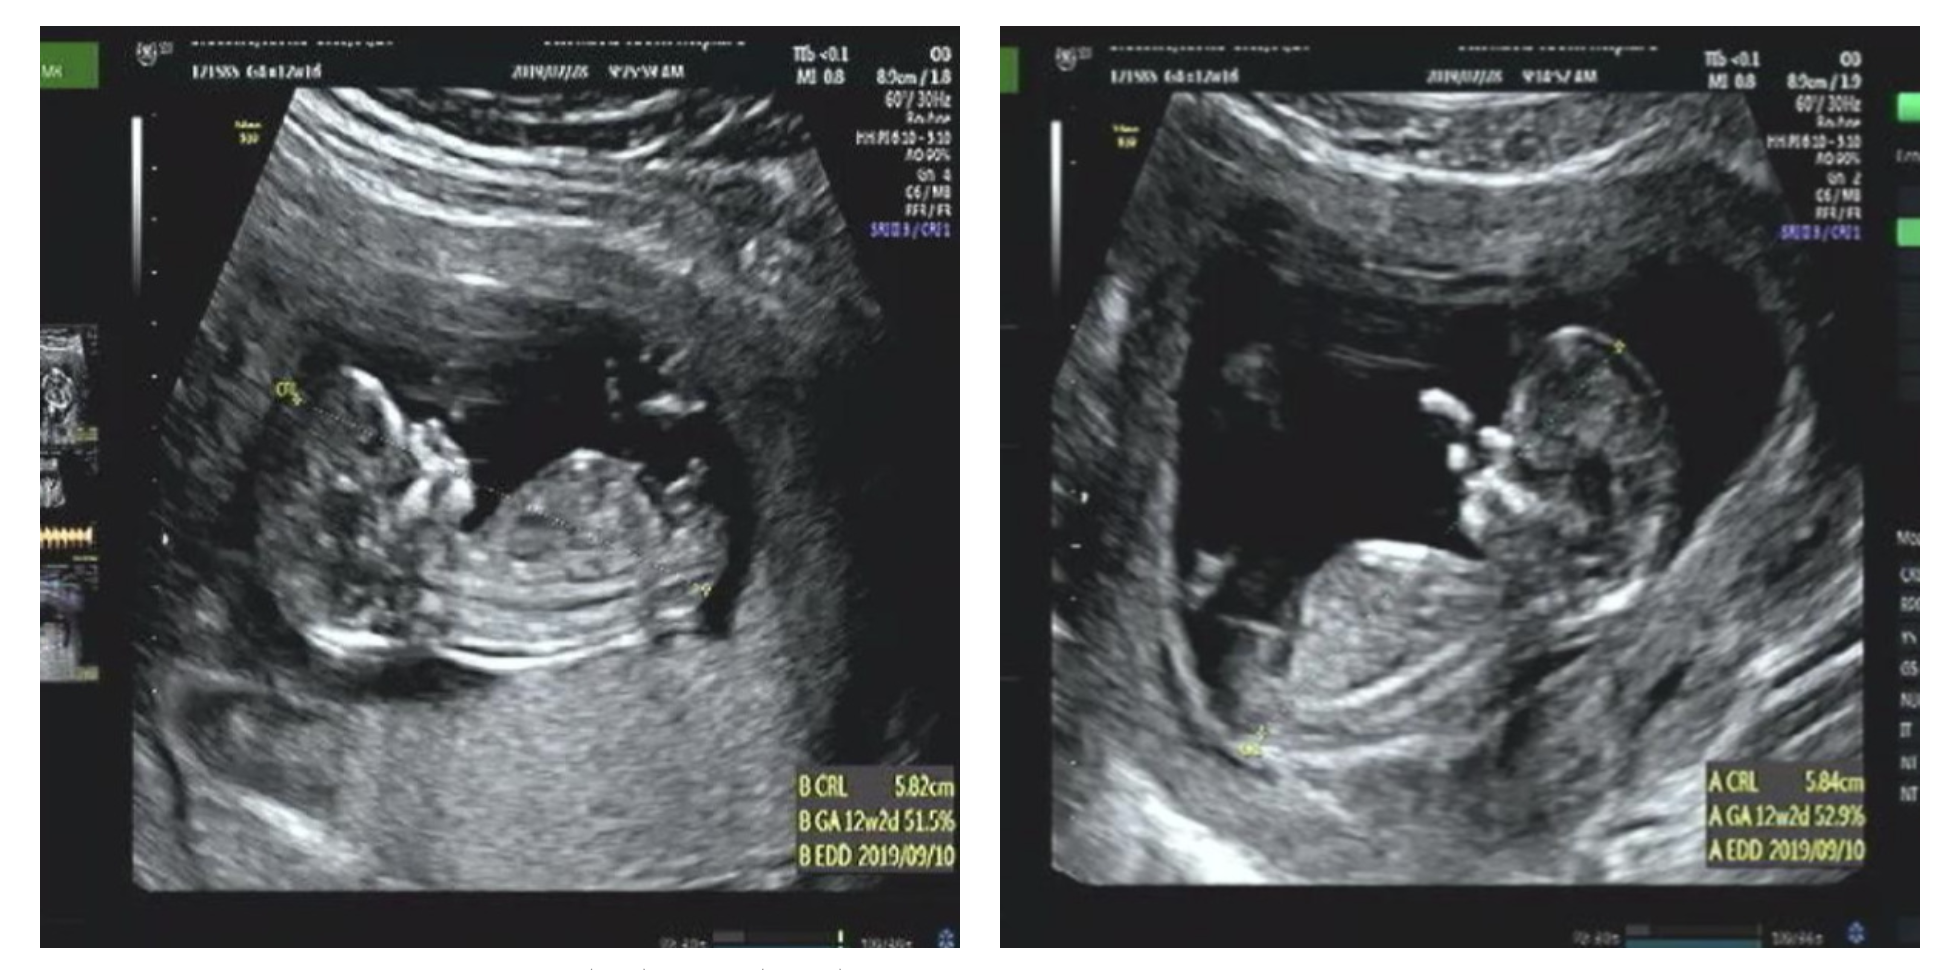

지금 보면 12주때부터 포도(왼쪽)보다 망고(오른쪽)의 양수가 눈에 띄게 많다. 망고는 양수가 많아서 둥둥 떠 돌아다니는 바람에 심장 소리 듣기도 힘들었다. 전조 증상 (개인적 의견)